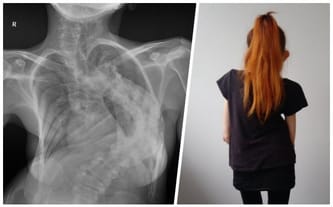

Ostatni krzyk kręgosłupa o pomoc! Skolioza zabija, Patrycja jest w niebezpieczeństwie!

Cel zbiórki: pilna operacja stabilizacji i resekcji kręgosłupa w Czechach

Skrzywienie udało się zmniejszyć do około 75 stopni. To nadal dużo i niewykluczone, że jeszcze będę potrzebowała kiedyś ponownej operacji. W tym momencie jednak jest nieźle, a co najważniejsze moje serce i płuca chociaż trochę odetchnęły.